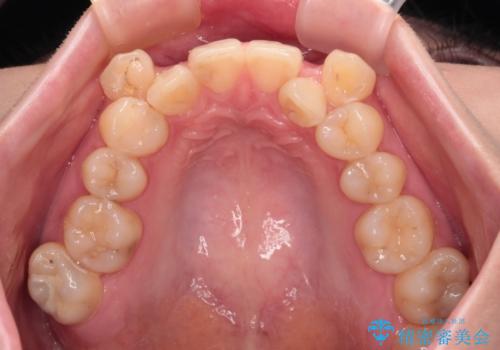

上下の八重歯とクロスバイト ワイヤー装置での抜歯矯正

- 八重歯とクロスバイトを気にして来院された患者様です。

上下ともに八重歯が顕著であり、前歯のクロスバイトがあったため、上下左右の第一小臼歯4本を抜歯し、ワイヤー装置での抜歯矯正を行うこととしました。